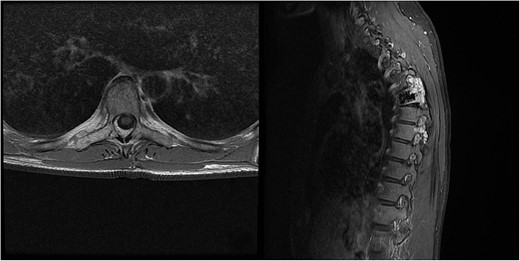

We decided to perform a revision total en bloc spondylectomy at Th6, along with resection of the Th8 pedicle and costovertebral joint, with a partial resection of the adjacent rib. Posterior spinal fixation from Th3 to Th10 was performed using radiolucent carbon screws, and the Th6 body was reconstructed using a radiolucent expandable cage (Figs 3 and 4). During the surgery, MEPs and SEPs were lost, with the patient waking up paraplegic (ASIA score B, VAS pain score 5). Immediate postoperative MRI showed no residual signs of thoracic spinal cord compression due to tumour or haemathoma (Fig. 5). The patient’s neurological status substantially improved the day after surgery, and thereafter, gradually improving over the next few days, allowing the patient to walk independently within 10 days (ASIA score D, VAS pain score 3). A multidisciplinary council decided against postoperative radiotherapy to avoid aggravating neurological symptoms by possibly causing additional damage to the myelopathic spinal cord. On the 11th postoperative day, the patient reported dyspnoea, and urgent CT angiography revealed peripheral pulmonary embolism, which was managed utilizing Deltaparine. Subsequent postoperative course was uneventful, leading to his discharge on the 15th postoperative day, ambulating independently using a walker. MRI follow-up was conducted 6 months postsurgery, followed by yearly checks. At the last follow-up, 2.5 years after the second surgery, there were no signs of tumour recurrence, and the patient exhibited no gait disturbance, back pain, or radiological signs of spinal instability (Fig. 6) (ASIA score E, VAS pain score 0).

Final follow-up X-Ray scan and MRI imaging showing no radiological signs of spinal instability or myelopathy.